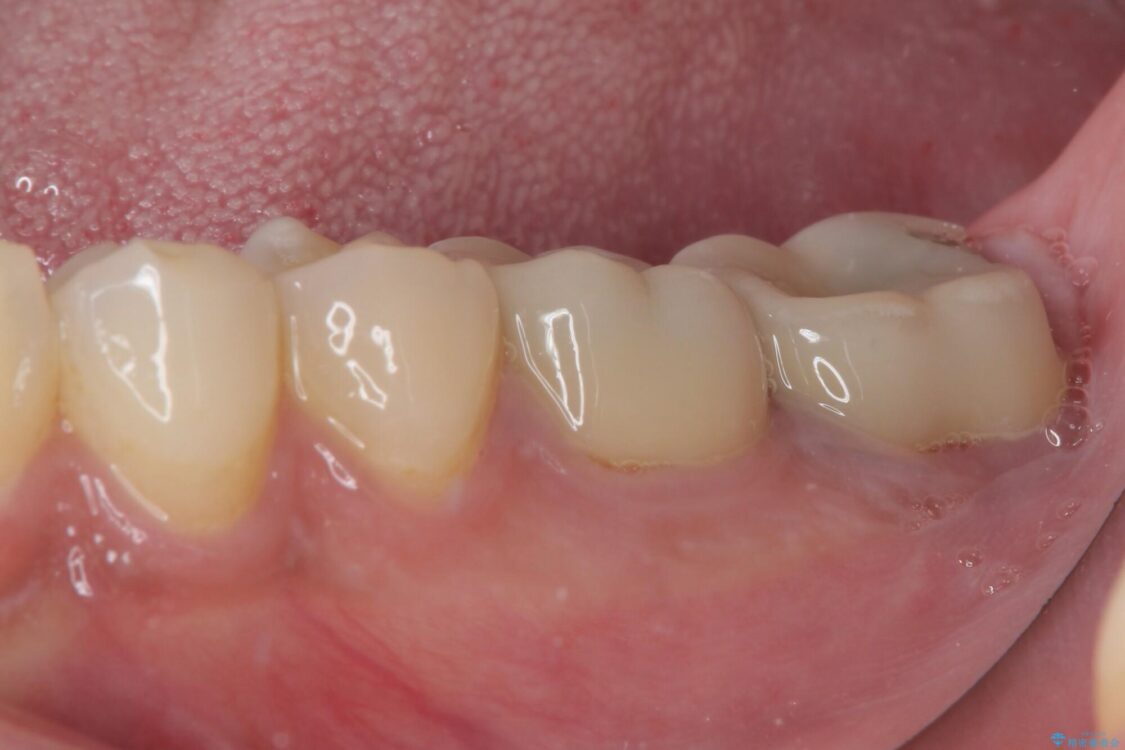

間もなく海外赴任という状況で奥歯のクラウンが割れてしまったとのことで来院された患者様です。

下顎の1番奥の歯であり、歯肉に覆われている部分が大きいためセラミックの十分な厚みが取れない状態でした。

強化セラミックを用いたオールセラミッククラウンにて補綴治療を行うこととしました。

十分な土台の高さを確保できない状態であったので、維持力のある土台の形態に整えることで、極力長持ちする治療を心がけました。

治療途中